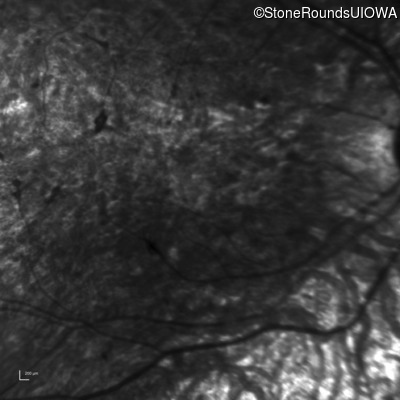

Infrared Fundus Photograph - Right - 5/200

Exemplar